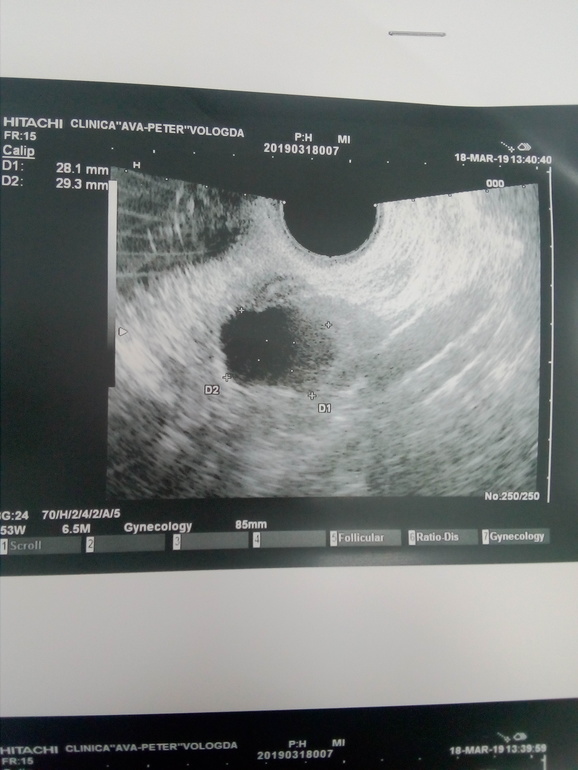

Здравствуйте девушки. Ситуация следующая. Идет первый цикл стимуляции клостилбегит по 1 таб в день со 2 по 6 дц. Врач сказала что перед приемом узи делать не надо, первое через пару дней после последней таблетки. Сегодня пошла на узи и пипец... На левом яичнике киста 29мм. Видимо с прошлого цикла. ХЗ что делать то теперь??? Можно кто сталкивался с таким.

Фото узи

Была на узи на 13 дц киста уже порядком уменьшилась. Во втором Я ДФ был 24мм, но походу он регресировать начал тк стенки были уже не ровные. Я стимулировалась без укола, вот и О не было. ЖДу начало след цикла и снова на стимуляцию, но теперь то схожу и посмотрю что и как до таблеток еще

Спасибо за ответ. Вот и не знаю что и думать. В принципе думаю вряд ли так фолик быстро вымахал. Я переживаю за то что не начала бы киста еще больше расти. Вот еще смущает что она почему то на узи как то не как киста выглядит, что то уж больно края не ровные

Теперь то буду знать. Я что сейчас делать не знаю. Странно что киста не ушла с М. была киста в первом цикле после лапары и ушла после М. И как то уж она выглядит странно, края не ровные какие то.